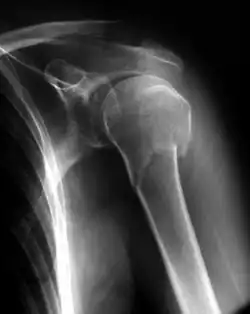

Fratura óssea

Fratura óssea é uma situação em que há perda da continuidade óssea, com a separação de um osso em dois ou mais fragmentos após um traumatismo.

Classificação

As fraturas podem ser classificadas de acordo com vários critérios.